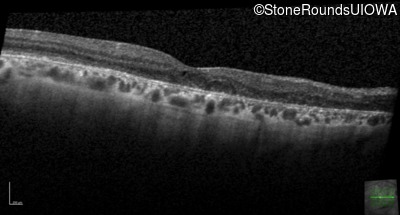

Foveal Hypoplasia (IIIG)

Highlighted Images

Diagnosis & molecular findings

Foveal Hypoplasia PAX6 Pro76Leu CCG>CTG   AD